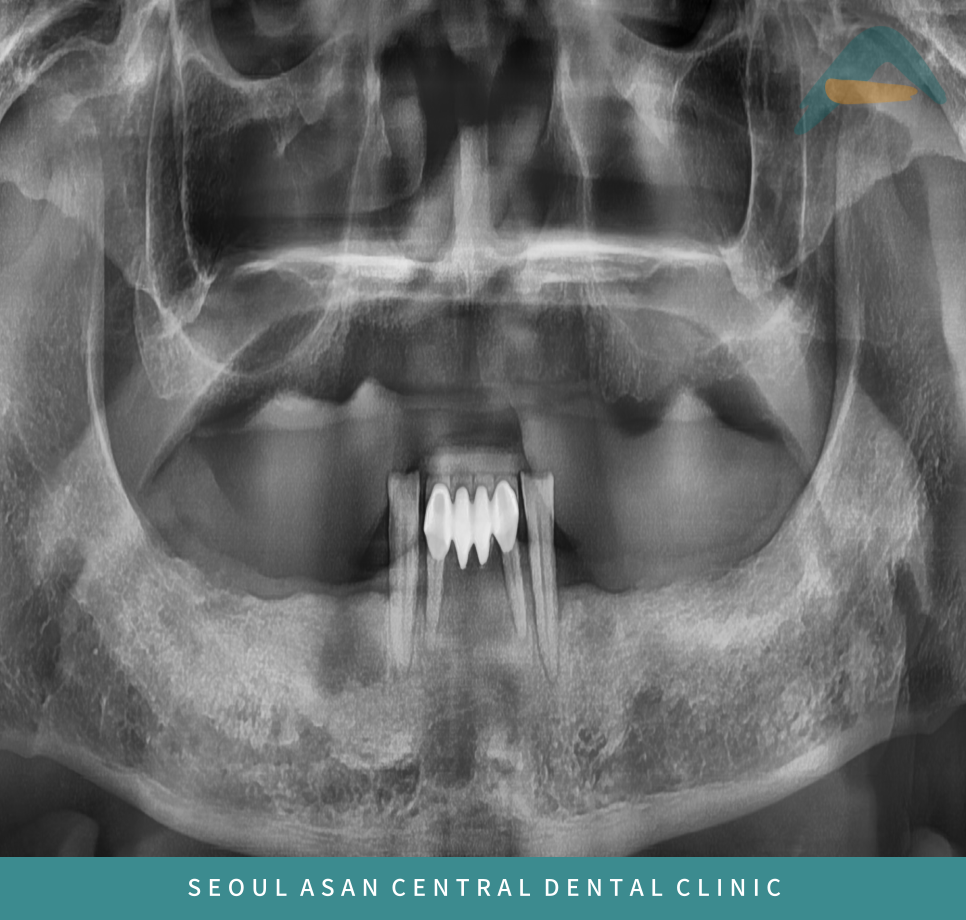

성남치과에서는 정밀한 검사를 위해 파노라마 사진을 촬영하여

이를 통해 잇몸뼈가 소실되어 있는지 확인을 합니다.

위 파노라마 사진처럼 위턱의 양측 어금니 부위는 상악동이 많이 내려와 있으면

상악동 거상술을 동반한 임플란트 식립이 필요할 수 있습니다.